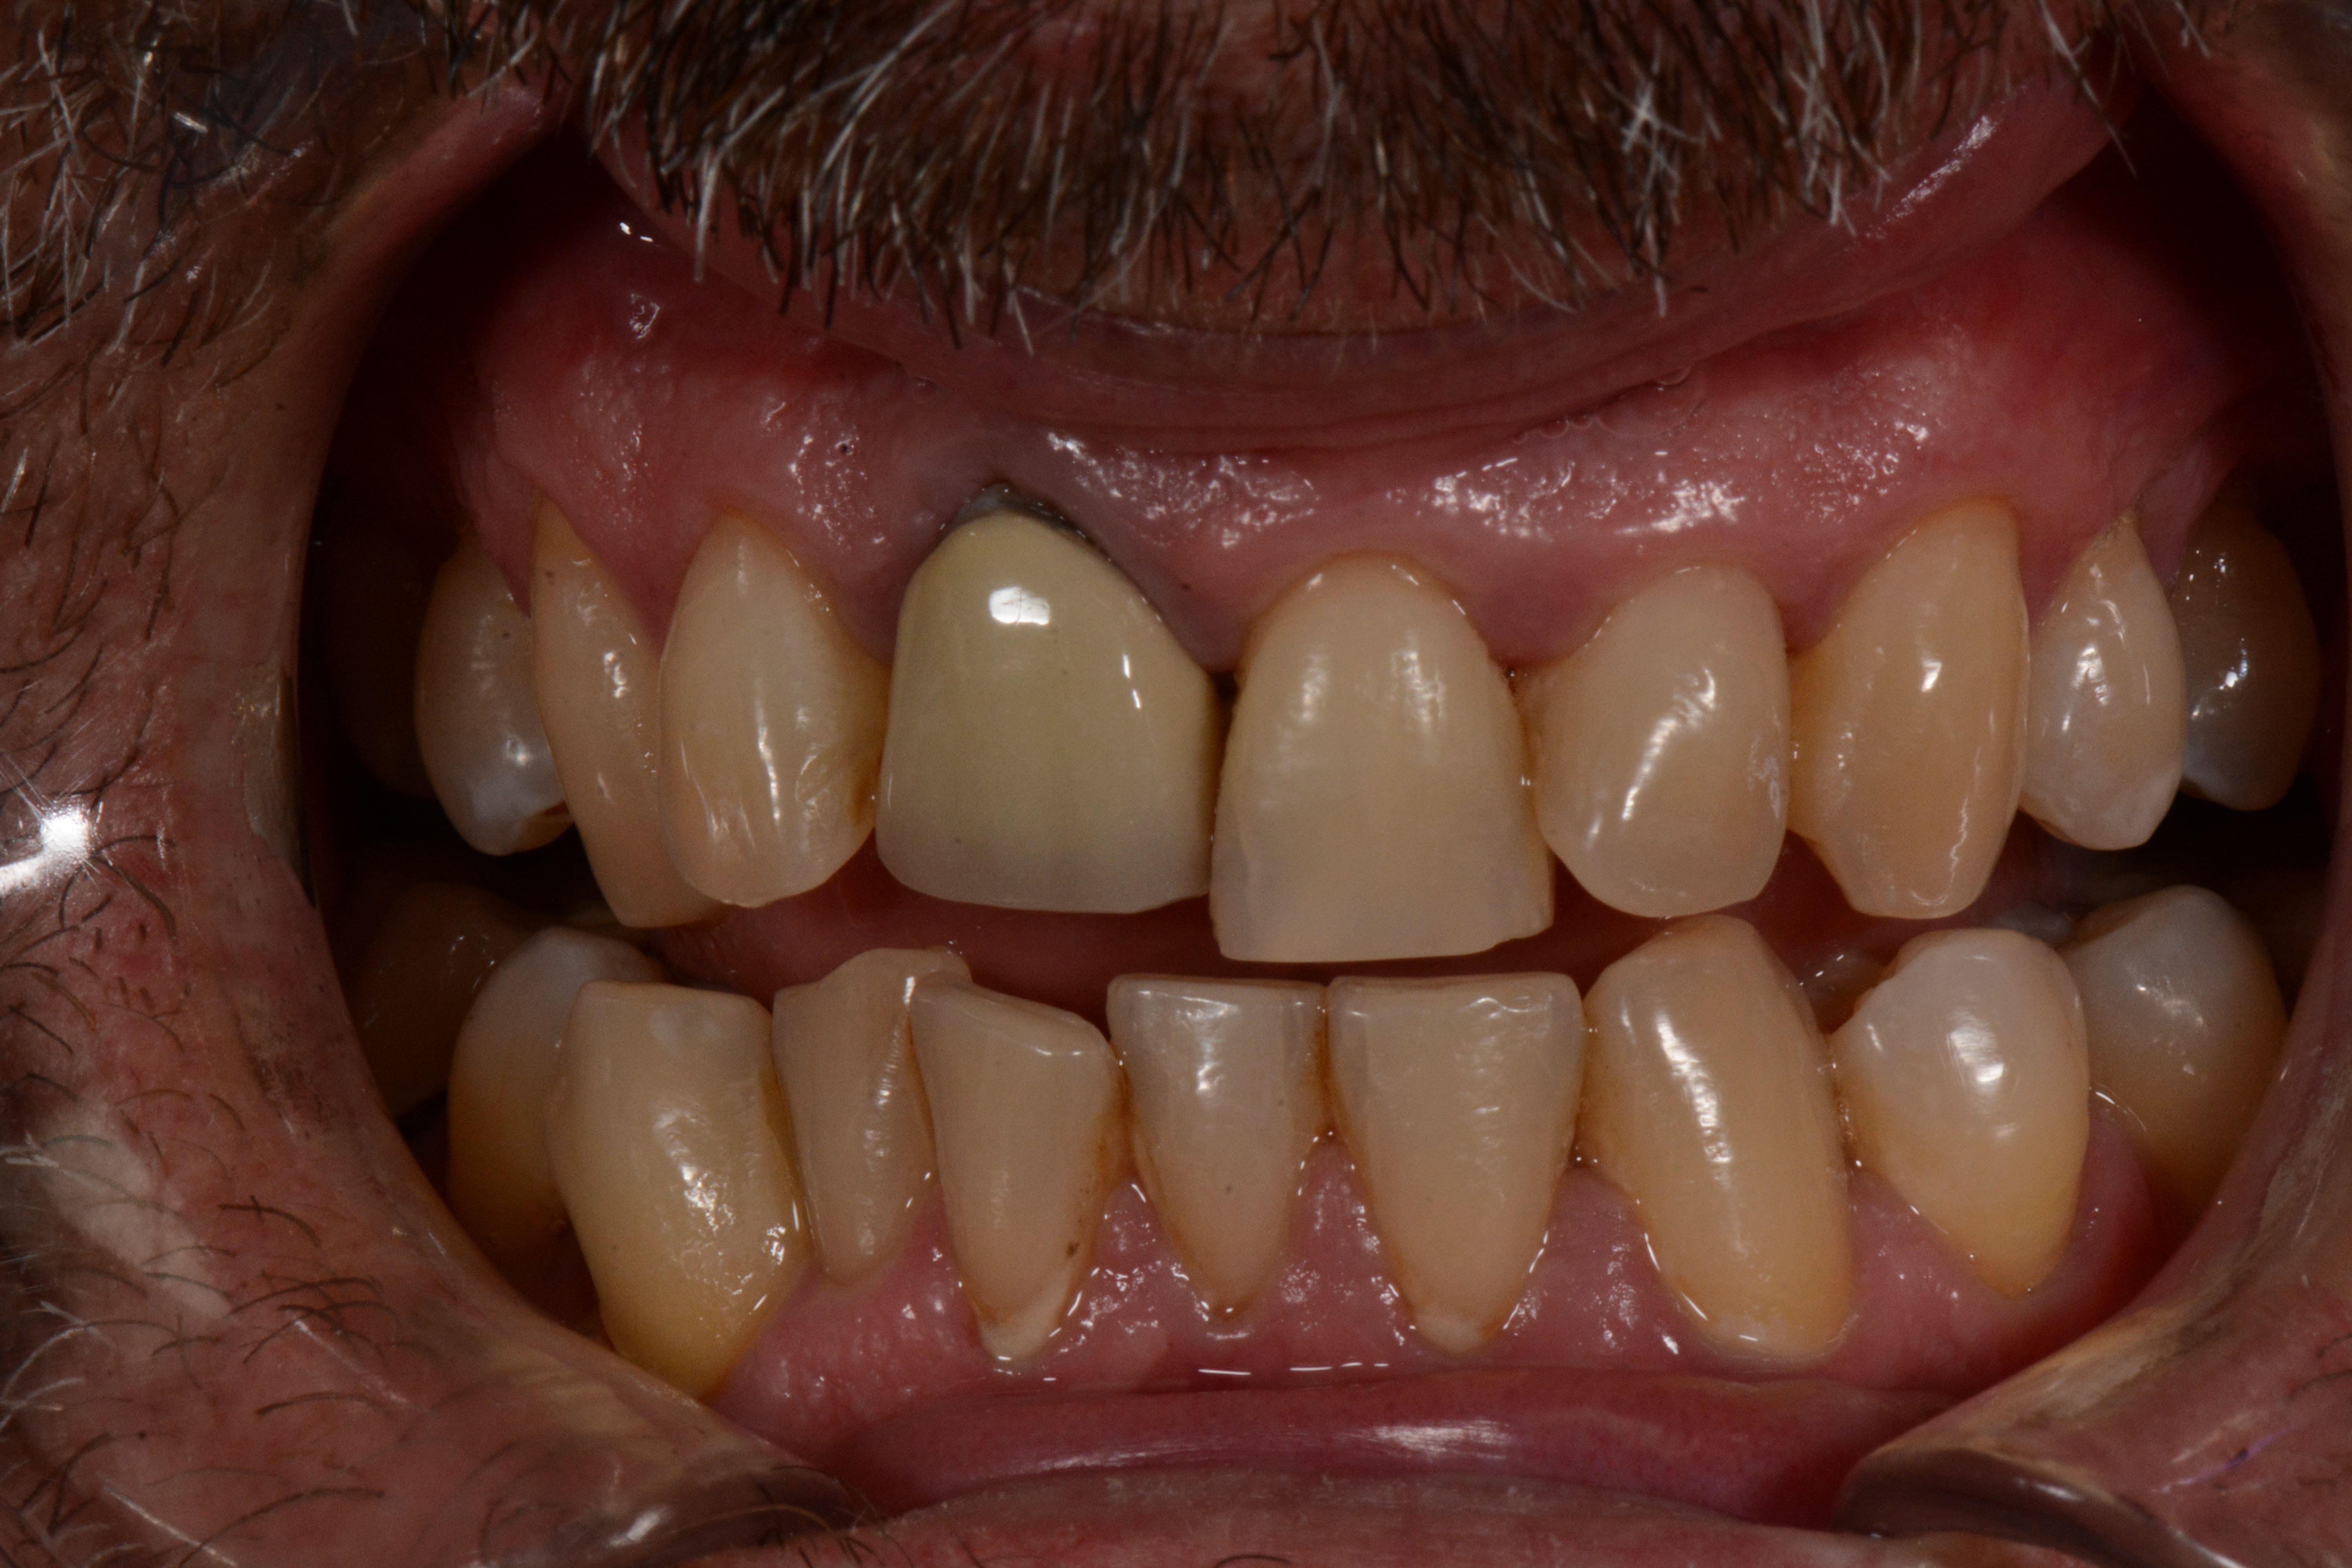

Bonjour, je poste ici pour partager un cas rencontré au cabinet, malheureusement une seule photo succinte.

Depuis 2 ans il porte à la mandibule une gouttière partielle 18h/24 (des cales amovibles postérieures reliées par une barre linguale en résine), je n'ai pas la photo. Cela a soulagé ses douleurs chroniques. Cependant à l'examen je constate des contacts en PIM uniquement sur les 7.

Les photos antérieures que m'a présenté le patient semblent indiquer qu'il était en classe II.2.

ensuite plus que la cl2.2 c est l occlusion croisée qui est genante .

et le pompon , c est la face palatine de la 11 qui interfere sur celle du bas .

peu importe ç est un pb de decalage lateral ,

pcq tu remarqueras que sont atm gauche est frit bouilli ,